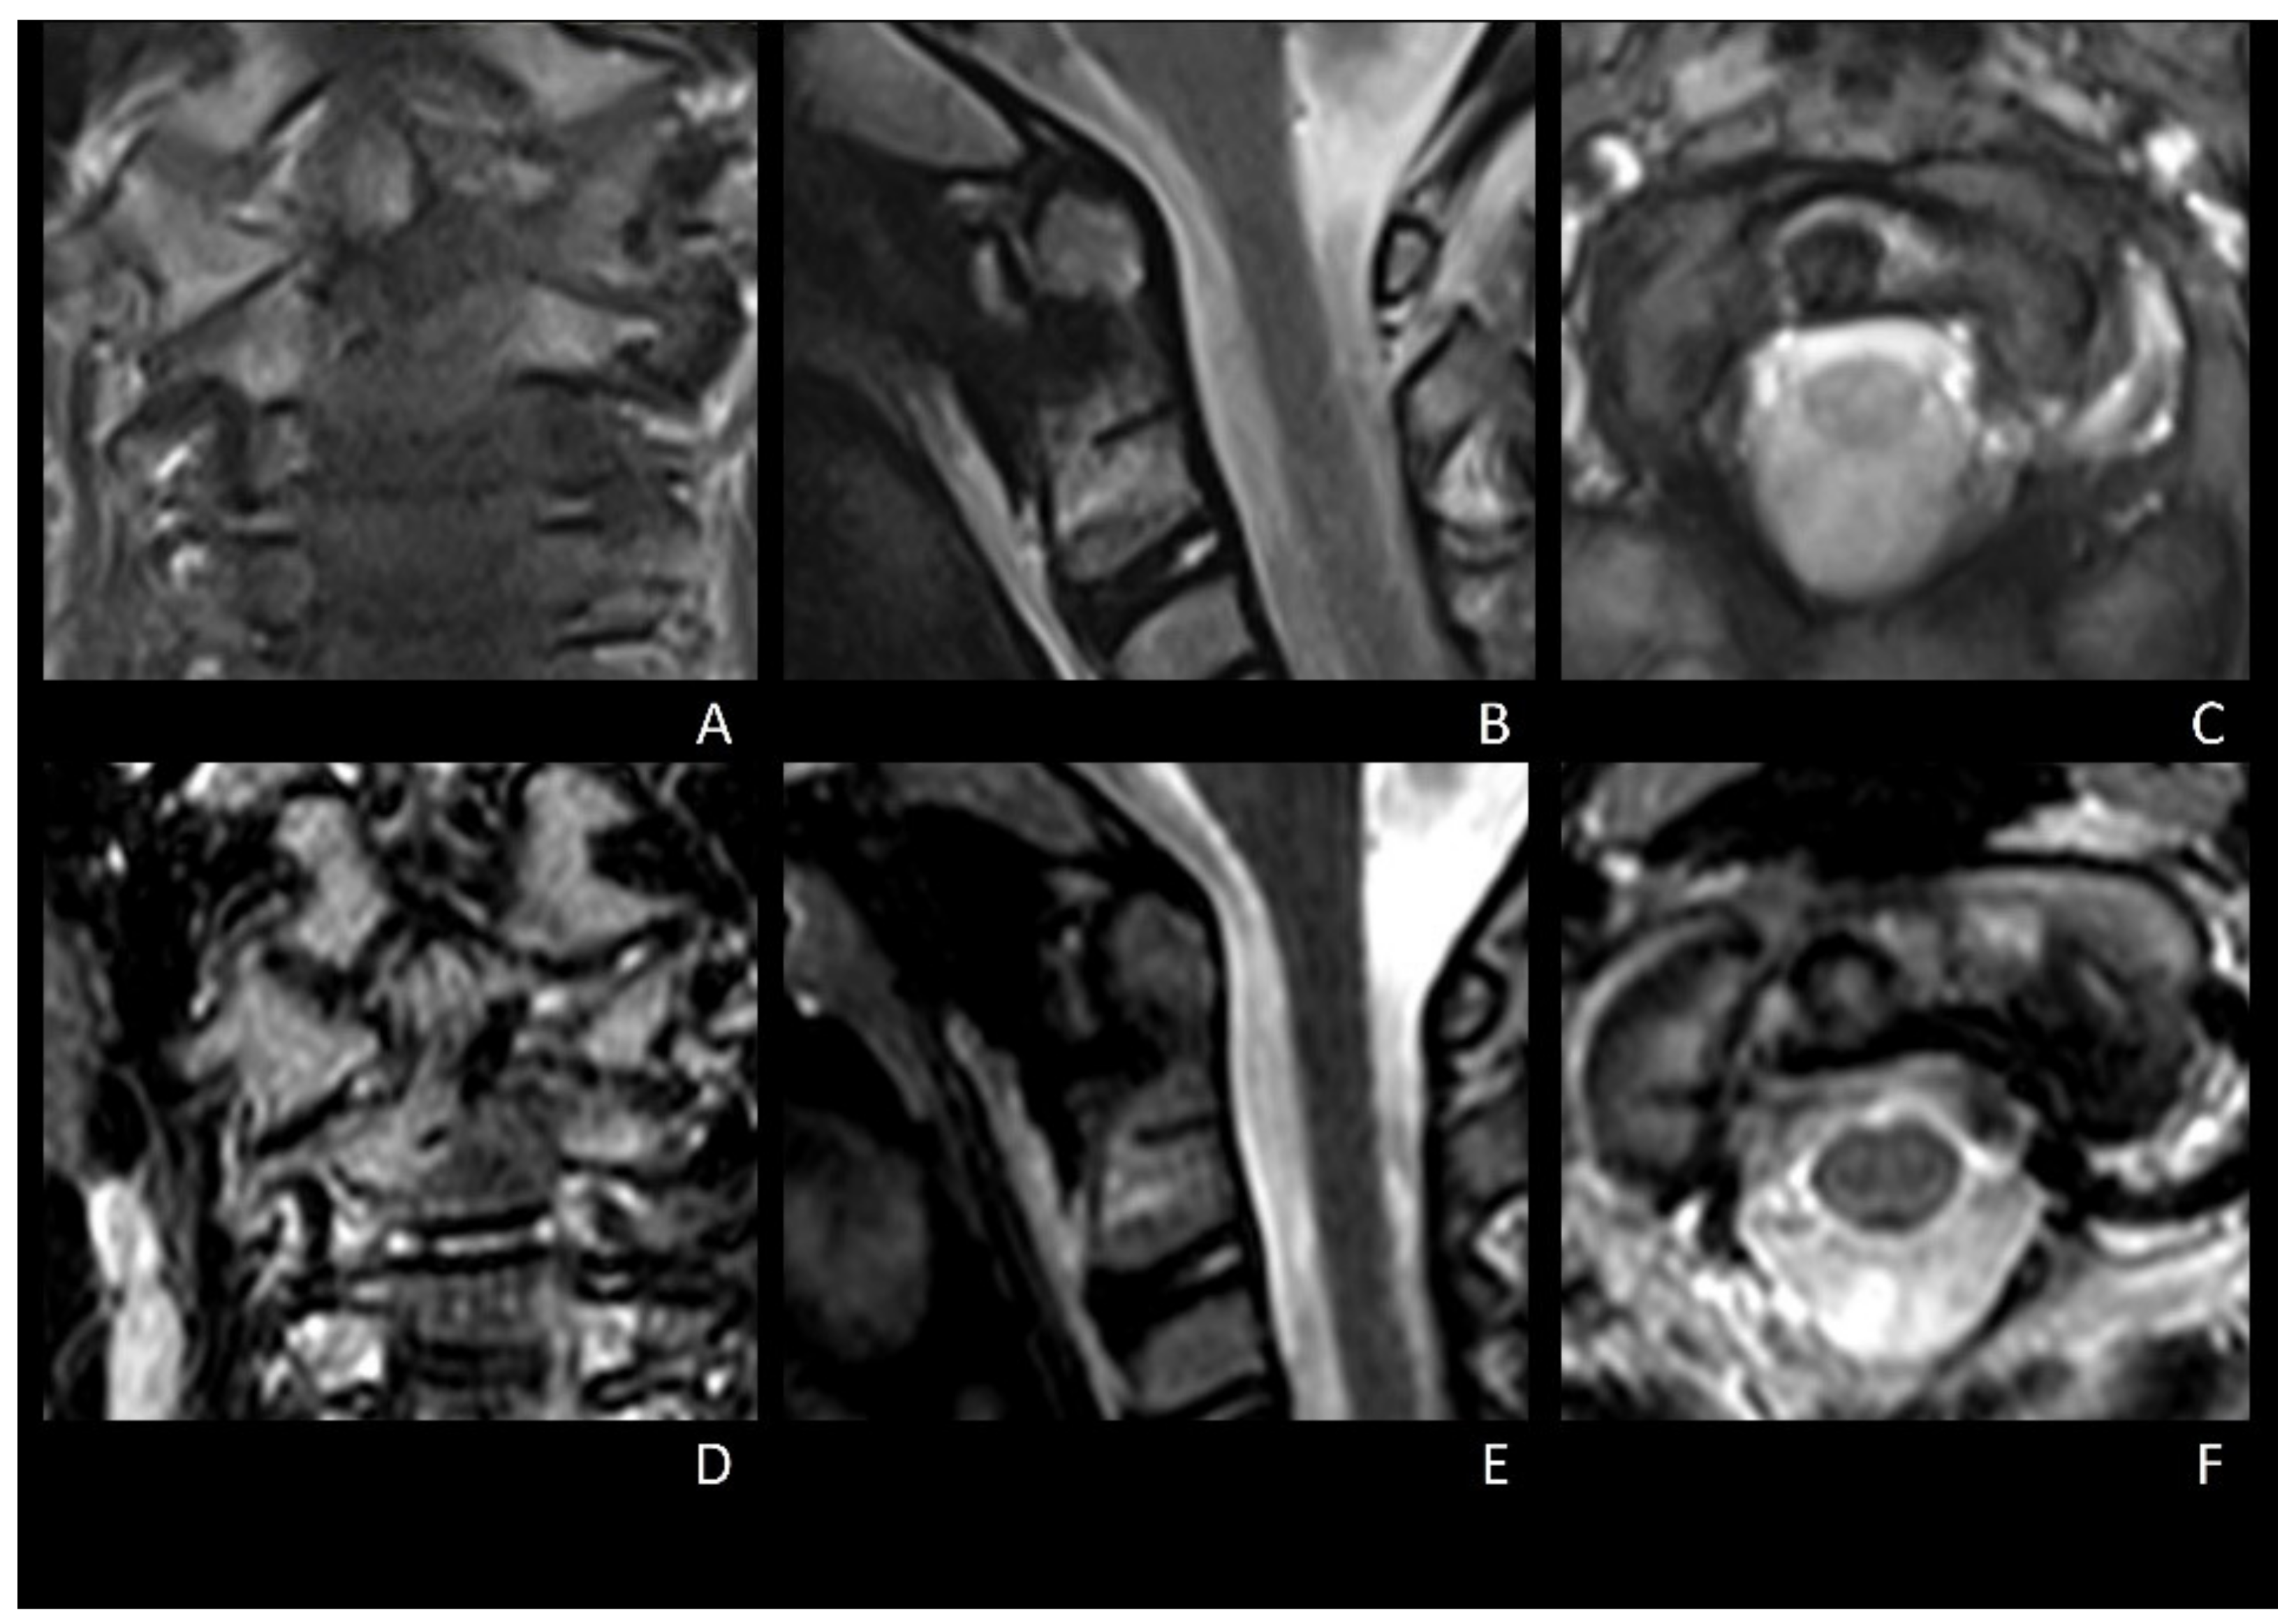

2.1.1. Clinical Presentation, Diagnosis, and Initial Conservative Therapy

2.1.2. Surgical Procedure